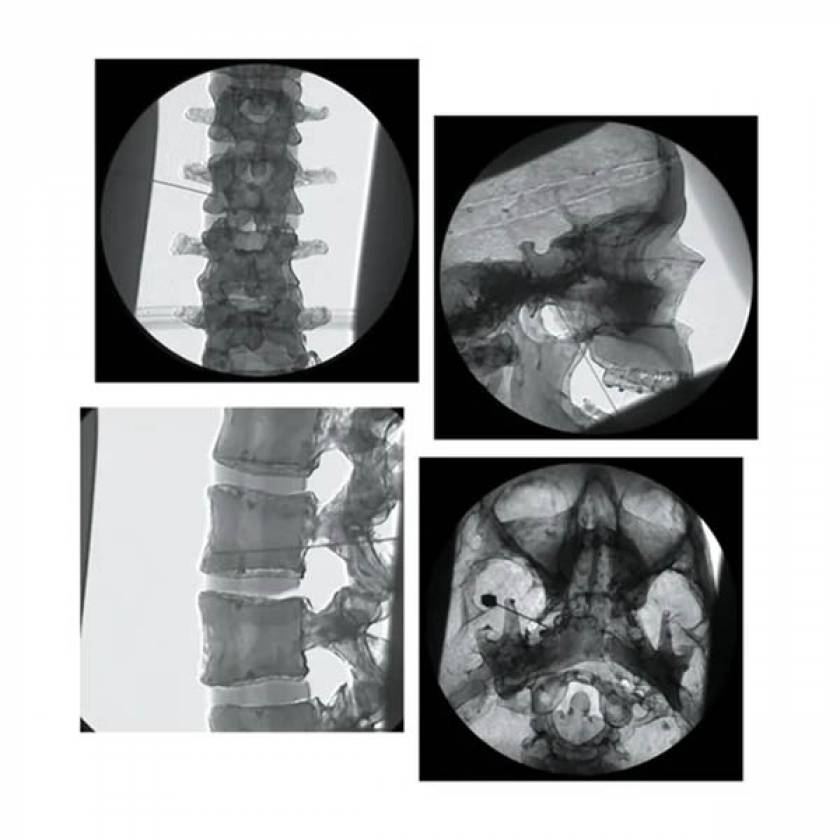

Procedure of the Week Lumbar Sympathetic Block Pain Management Block Pain Relief Nerve blocks ease pain by offering immediate relief. Nerve blocks are an effective way to prevent, reduce, or manage pain. They disrupt pain signaling around the body. Discuss these with your healthcare provider. Unlike peripheral nerve blocks, epidurals offer temporary relief and may require multiple treatments. A nerve block may be used to treat some kinds of chronic pain. Often. Block Pain Relief.